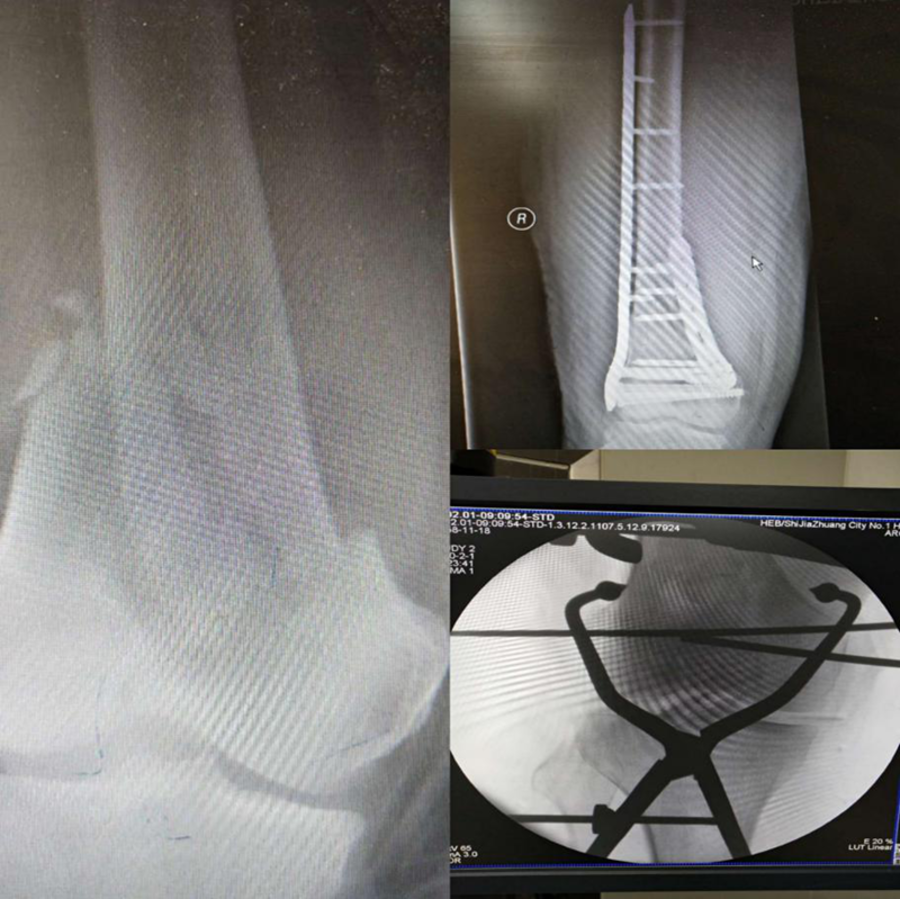

骨科劉曉輝主任完成的骨折復(fù)位內(nèi)固定手術(shù)